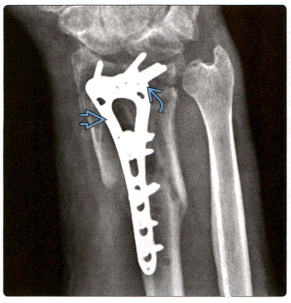

1. Косая рентгенограмма показывает: фиксированная ладонной пластинка, винты и имплантаты вышли из строя.